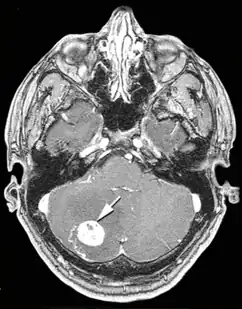

Description de l'image Hemangioblastoma cerebellum.jpg.

L'hémangioblastome est une tumeur vasculaire bénigne[1], à croissance lente. Elle est souvent rencontrée dans le cadre d'une maladie héréditaire, la maladie de von Hippel-Lindau. Elle en est la composante axiale. L'hémangioblastome est trouvé le plus souvent dans la fosse postérieure, au niveau du cervelet.